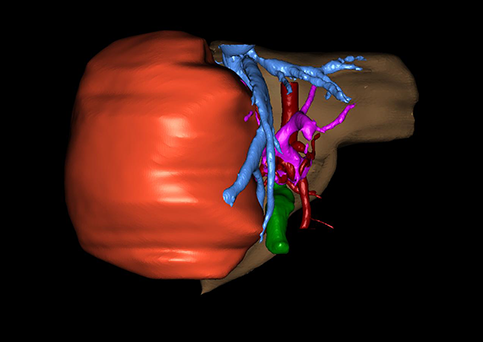

近年来由于数字医学的发展,基于可视化三维重建技术的计算机辅助手术系统极大推进了小儿肝脏肿瘤的精准手术的进步。可以立体透视肝脏解剖、精确掌握肝段的边界、精确测算肝段乃至任意血管所支配的功能体积、准确定位病灶及其与邻近血管的解剖关系,最终对不同手术方案进行比较、筛选和优化。因此,计算机辅助手术规划系统是实现精准肝切除的有力辅助工具,是未来数字外科、精准外科等21世纪外科新理念的重要技术支撑。

计算机辅助手术规划系统具有良好的操作可行性、计算准确性和三维显示效果,可半透明、交互式显示真实的肝内立体解剖关系和空间管道变异,准确计算肝内管道的直径、走行角度,两点间的垂直距离,和任意血管的支配或引流范围等传统二维影像无法获取的信息,有助于实施个体化手术,提高了手术的确定性、预见性和可控性。计算机辅助手术规划系统可直观显示预留肝脏的结构和功能,并可通过虚拟切割功能辅助术者对手术方案进行蹄选和优化,系统评估手术风险和制定对策,改变了部分二维规划的术式和切除范围,使部分二维规划认为不能切除的患者成功手术,提高了手术的根治性、安全性和病变的可切除性,更加符合精准肝脏外科的术前规划要求。详见第11章。

随着计算机技术及影像检查技术的不断发展,以精确的术前影像学和功能评估、精细的手术操作为核心的精准肝切除技术日益受到重视。基于数字医学的计算机辅助手术技术(computer-assisted surgery,CAS)则是实现肝脏精准手术操作的基础。计算机辅助手术系统(CAS)可将术前二维(two dimensional,2D)的CT/MRI影像数据进行三维(three dimensional,3D)重建,建立个体化的肝脏三维解剖模型,清晰显示肝脏内脉管系统的走行及解剖关系,还原病灶与其周围脉管结构的立体解剖构象,准确地对病变进行定位、定性和评估,制定合理、定量的手术方案,实施个体化的肝脏血管取舍分配方案及实施精准肝脏手术。一般认为CAS包括:创建虚拟的患者的图像;患者图像的分析与深度处理;诊断、手术前规划、手术步骤的模拟;术中实时导航。应用本技术后,由于可以更清晰地看出肿瘤的界限,特别是根据肝血管的显影,判断出肿瘤与门静脉及肝静脉的关系以在手术前较准确地估计出手术成功切除的可行性。以往部分根据普通强化CT判断无法手术的病例而被评估为可以成功切除并手术成功。